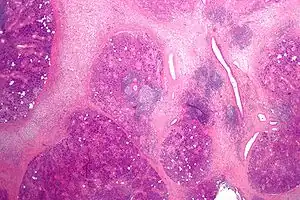

The gland is internally divided into lobules. Blood vessels and nerves enter the glands at the hilum and gradually branch out into the lobules.

Acini

Secretory cells are found in a group, or acinus. Each acinus is located at the terminal part of the gland connected to the ductal system, with many acini within each lobule of the gland. Each acinus consists of a single layer of cuboidal epithelial cells surrounding a lumen, a central opening where the saliva is deposited after being produced by the secretory cells. The three forms of acini are classified in terms of the type of epithelial cell present and the secretory product being produced - serous, mucoserous, and mucous.[17][18]

Ducts

In the duct system, the lumina are formed by intercalated ducts, which in turn join to form striated ducts. These drain into ducts situated between the lobes of the gland (called interlobular ducts or secretory ducts). These are found on most major and minor glands (exception may be the sublingual gland).[17]